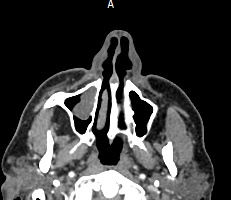

Одним из методов диагностики заболеваний носоглоточной области является мультиспиральная компьютерная томография. Методика предусматривает использование рентгеновского излучения. Благодаря различной способности тканей поглощать рентгеновские лучи и последующей цифровой обработке полученных данных, удается получить изображения исследуемой зоны в мельчайших подробностях. Рентгеновские лучи лучше всего поглощаются плотными тканями, такими как костная ткань, поэтому кости хорошо видны на снимках КТ.

При необходимости улучшения визуализации мягкотканных структур и особенно при подозрении на опухолевый процесс, применяется внутривенное болюсное контрастирование. Йодсодержащее контрастное вещество вводится пациенту в вену, после чего оно попадает в кровеносную систему и с током крови разносится по организму. Патологические очаги в большей степени накапливают контраст, что на снимках придает им детальность и яркие очертания на фоне окружающих здоровых тканей.

Инновационные цифровые приложения томографов позволяют получить снимки высокого качества и детализации, а также создать трехмерные реконструкции анатомической зоны исследования, что дает возможность рассмотреть пространственное расположение органов и патологических образований. КТ носоглотки с контрастом назначают при подозрении на рост новообразований, в случае хронического воспаления, при врожденных аномалиях строения носа и прилегающих к нему придаточных пазух.